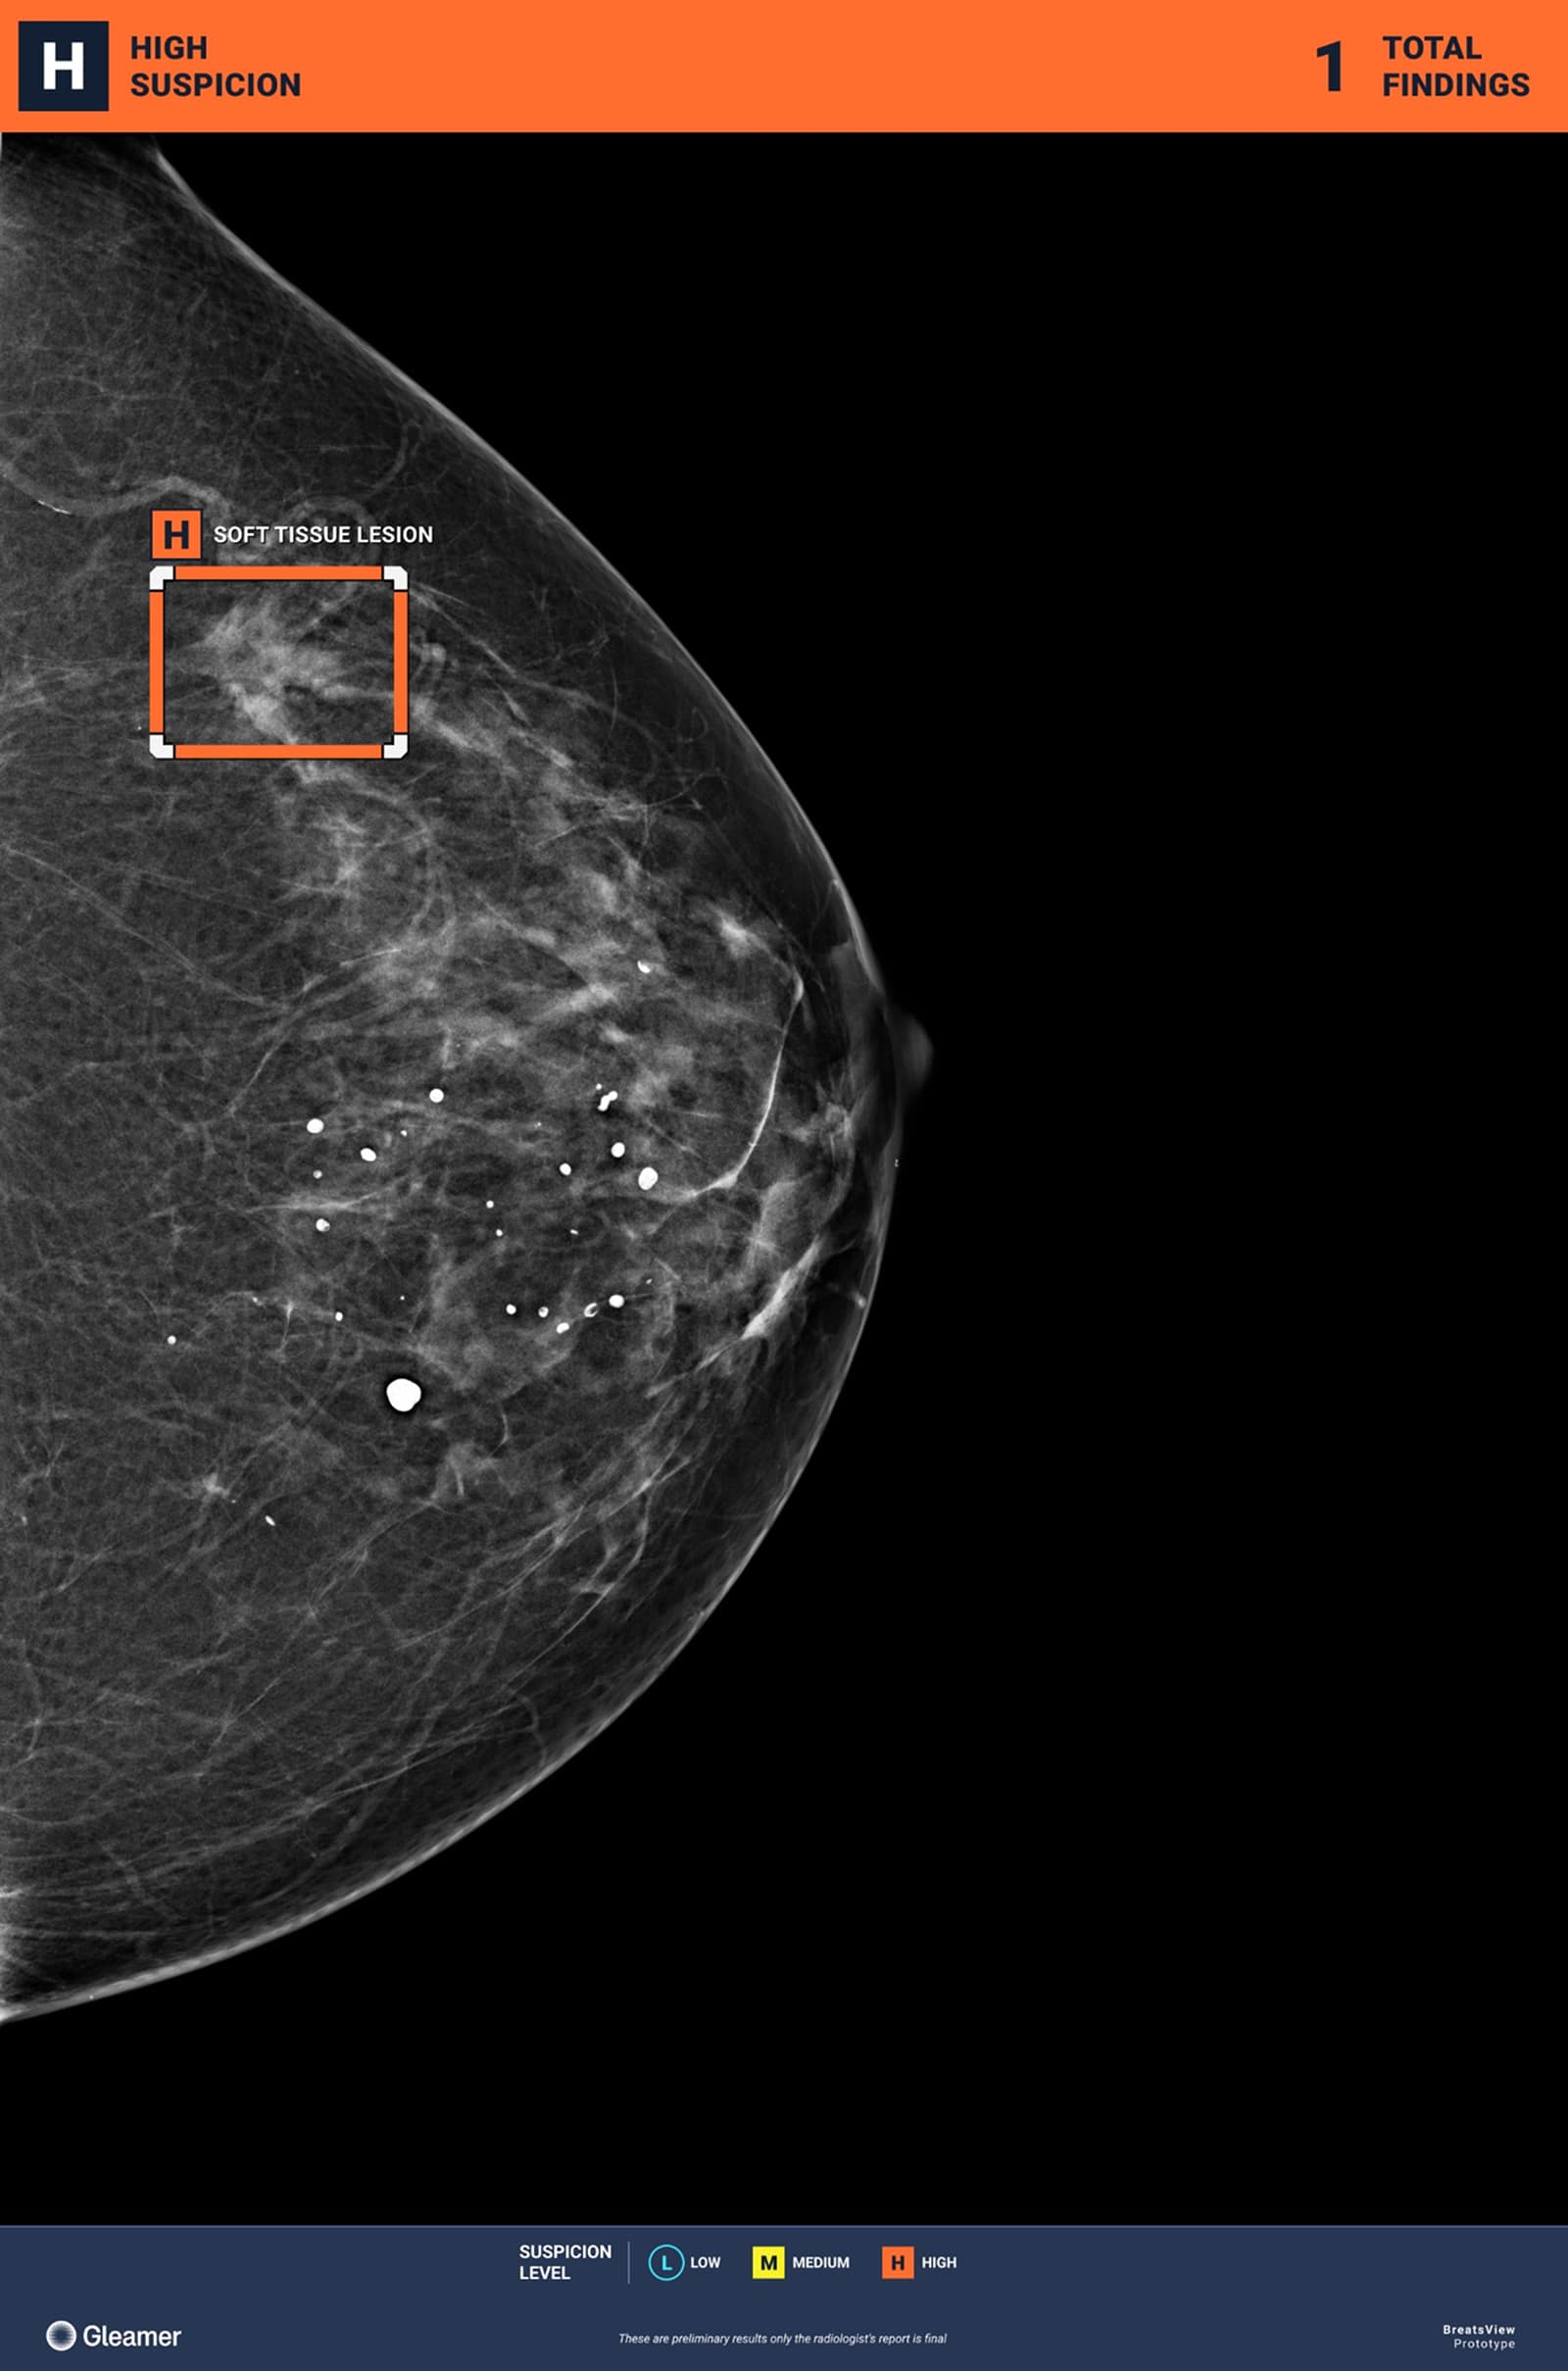

Convinced that AI raises quality standards in the healthcare field while contributing to increased reliability in diagnoses, Gleamer is pursuing a two-pronged expansion strategy. On the one hand, the company is expanding its catalog to cover all imaging modalities. After establishing its expertise in standard radiology with several certified products, the company is deploying its new medical devices for mammography and CT scans, with MRI as the next step.

In fact, the clinical performance of Gleamer's solutions demonstrates the transformative impact of AI in radiology. Validated by over 30 scientific publications, they show an average improvement of 30% in lesion detection, allowing general radiologists to reach the level of specialists. And unlike human expertise, which can falter during night shifts or after long hours, AI maintains this constant level of excellence, guaranteeing optimal diagnostic quality 24/7.